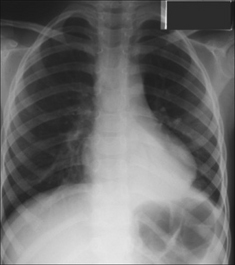

3. There is a pyrexia.

image Pneumonia can induce or increase symptoms.

image

Figure 29.5 Acute asthma. Unexpected clinical deterioration. Left-sided shadowing effaces the heart border. Pneumonia. The consolidation—pneumonia—is situated in a lingular segment of the left upper lobe.